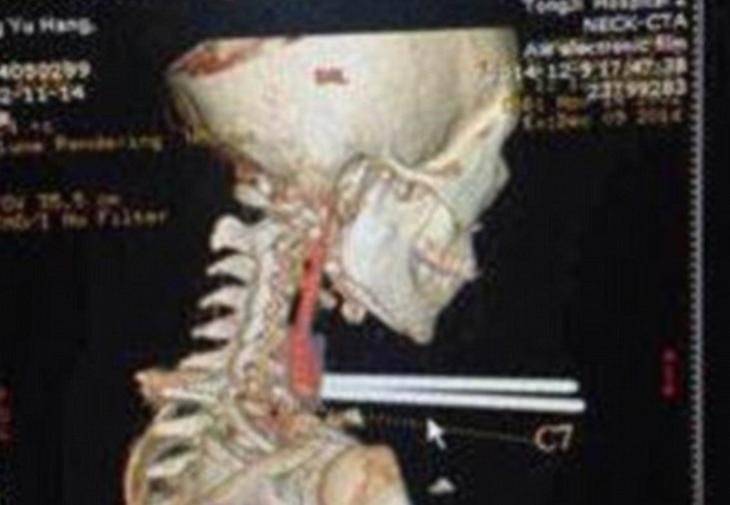

Junio Chia originario de la ciudad de Wuhan (China) sufrió un terrible accidente; el chico de 12 años recibió un codazo en la espalda mientras comía fideos; lo que provocó que se le clavaran dos palillos de metal.

El personal de la escuela llamó a una ambulancia y el niño fue trasladado de urgencia al hospital. El médico que lo atendió Zhou Jen, afirmó que no se le dañó la tráquea, ni los vasos sanguíneos del esófago.

De todas formas, explicó que la única complicación fue el material del palillo ya que como son de metal hay riesgo de infecciones. Por esa razón, el niño todavia permanece internado.